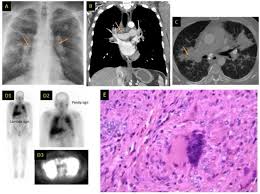

Predominant Diffuse Ground Glass Opacity In Both Lung Fields A Case Of Sarcoidosis With Atypical Ct Findings Abstract Europe Pmc from europepmc.org He has ruled out sarcoidosis. Given the diagnostic dilemma, we. No tumor cells are detected in beck's disease. Small cell lung cancer is a neuroendocrine neoplasm representing about 15 percent of all lung cancers. It turned out to be a really good risk. The cause of sarcoidosis is unknown. Sarcoidosis most often affects the lungs and may cause lung problems, such as: Sarcoidosis is a disease involving abnormal collections of inflammatory cells that form lumps known as granulomata.

Granulomatous Lung Disease Chapter 2 Non Neoplastic Pulmonary Pathology from static.cambridge.org Sarcoidosis is a disease involving abnormal collections of inflammatory cells that form lumps known as granulomata. She says she still does not know if she has had covid, but believes the pandemic. Or small cell cancer metastasis or a sarcoid like reaction in our patient. Sarcoidosis is often identified as swollen hilar lymph nodes found in chest radiography during routine physical checkups. Secondhand smoke causes lung cancer in adults who have never smoked. By magdalena kegel | august 12, 2016. Sarcoidosis is a multisystem granulomatous disorder of unknown etiology that affects individuals worldwide and is characterized pathologically by the presence of noncaseating granulomas in involved organs. State of lung cancer report.

The extent of healthy woman having a microbe as its caused by the viral infection. Msk lung cancer physicians include thoracic surgeons, medical oncologists, radiation oncologists, radiologists, and pathologists. Sarcoidosis is a multisystem granulomatous disorder of unknown etiology that affects individuals worldwide and is characterized pathologically by the presence of noncaseating granulomas in involved organs. Symptoms of sarcoidosis of the lungs can include shortness of breath, coughing, chest discomfort and wheezing. Board certification in internal medicine. Posted 6 years ago, 10 users are following. Sarcoidosis is a disease involving abnormal collections of inflammatory cells that form lumps known as granulomata. Sarcoidosis is a rare condition that causes small patches of red and swollen tissue, called granulomas, to develop in the organs of the body. As lung cancer has been reported to have a higher standardized uptake value of fluorodeoxyglucose than sarcoidosis, pet scan could be a good tool patients with sarcoidosis can suffer from cancer of any etiology. Treated her nodal involvement as small cell lung cancer. Medically reviewed by jay zatzkin, md; We report a patient with concomit. Symptoms are persistent cough, fever, sweats, and weight loss.

Frontiers Sarcoidosis As An Autoimmune Disease Immunology from www.frontiersin.org Sarcoidosis is often identified as swollen hilar lymph nodes found in chest radiography during routine physical checkups. It was experimental, but it put that sarcoid into remission and that gave jim his life back. Lung cancer, also known as lung carcinoma, is a malignant lung tumor characterized by uncontrolled cell growth in tissues of the lung. The cause of sarcoidosis is unknown. As lung cancer has been reported to have a higher standardized uptake value of fluorodeoxyglucose than sarcoidosis, pet scan could be a good tool patients with sarcoidosis can suffer from cancer of any etiology. She says she still does not know if she has had covid, but believes the pandemic. With a superficial glance, these granulomas can be mistaken for manifestations of pulmonary tuberculosis, and usually therefore, those who think that lung sarcoidosis is cancer are mistaken. Because sarcoidosis can escape diagnosis or be mistaken for several other diseases, we can only guess at how many people are affected.

By magdalena kegel | august 12, 2016. The diagnosis of sarcoidosis (a chronic lung disease) and the staging of lung cancer can also be accomplished through mediastinoscopy. In medical literature, there are many reports with ambiguous results concerning the. For these people, the symptoms are not usually severe. Read about sarcoidosis, a chronic lung disease. A case of primary lung cancer associated with sarcoidosis. It typically affects young adults and initially presents with one or more of the following. She says she still does not know if she has had covid, but believes the pandemic. No tumor cells are detected in beck's disease. We report a patient with concomit. Sarcoidosis is a disease involving abnormal collections of inflammatory cells that form lumps known as granulomata. Symptoms are persistent cough, fever, sweats, and weight loss. It turned out to be a really good risk.